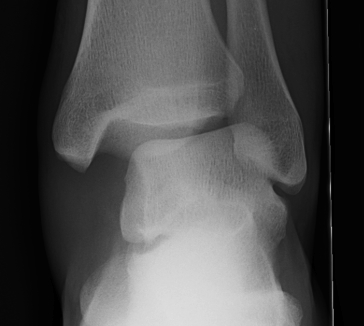

X-ray assessment

3 standard views

AP / Lateral / Mortise

Mortise

- AP with foot internally rotated

- should be symmetrical space around talus

Ankle Mortise ViewMortise

Increased tibio-fibular clear space  Overlap Increased medial clear space

Medial border of the fibula

Lateral border of the posterior tibia (incisura fibularis)

Measured 1 cm above the plafond

Overlap of the fibula and the anterior tibial tubercle

Medial talus to lateral medial malleolus

<5mm AP and mortise

> 6 mm AP view

> 1 mm mortise view

< 4mm

Equal to superior clear space

Syndesmotic injury Syndesmotic injury

Deltoid ligament injury

Lateral talar shift

Ankle AP Xray Syndesmotic Measurements Ankle Mortice Xray Syndesmotic Measurements Mortise

Lateral talar shift / increased medial clear space / deltoid ligament injury

Ankle Fracture Increased Medial Clear SpaceAnkle Fracture Increased Medial Clear Space 2Maisonnerve

Tibia / fibular overlap < 1mm / syndesmotic injury

Ankle Fracture Syndesmosis WidenedAnkle Diastasis